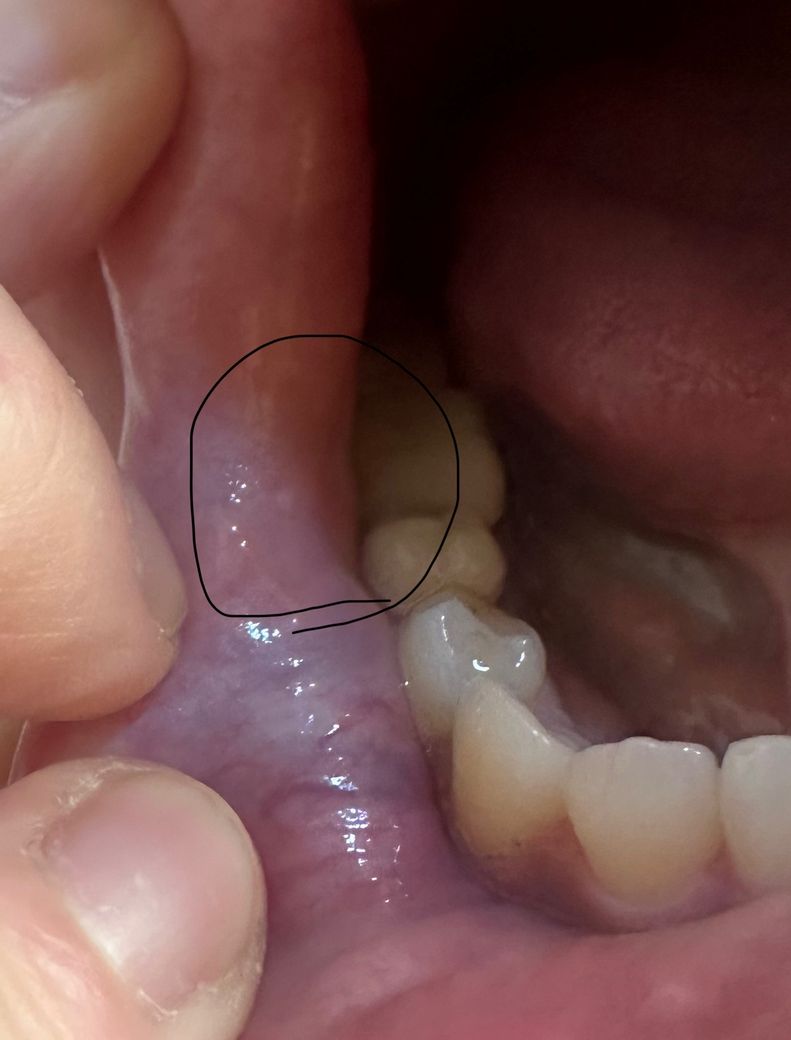

입술 끝 라인 바로 안쪽에 사진처럼 하얀 점(?) 같은게 있어요 미세하게 혀로 느껴져서 보니 사진처럼 하얀 점(?) 이 있습니다 기존 입술 끝 라인에도 하얀 점들이 몇개 있긴 한데 입술 볼 안쪽은 ㅠㅠ 모르겠어서요 ㅠ ㅠ 걱정 할 정도 인지 ㅠ ㅠ 시간 두고 지나면 사라질까요? 아님 그냥 둬도 되는건지

사진으로 보이는 현상은 크게 문제가 되지 않을 것으로 생각됩니다. 점막 조직 안에는 여러가지 조직들이 생성될 수 있는데 그중에서 지방 조직 같은 형태가 해당 사진처럼 보일 수 있습니다. 문제는 발생시키지 않지만 걱정이 되신다면 치과에서 진료를 받아보는 것을 권해드립니다.

제가 보기에는 피지선등의 정상조직 같습니다.

조직의 원래 형태일 가능성이 높으며 크기가 커진다면 내원해보시고 아니라면 신경안쓰셔도 될 듯 합니다.

볼살이 치아에 씹혀서 생긴거 같습니다. 큰 문제가 잇는건 아니니 너무 걱정하지 않으셔도 될것같습니다.

현재 구내염이 생긴 것으로 보이며, 보통 자연치유가 가능하며, 1~2주 정도 지나도 증상이 지속되거나 심해지면 병원진료를 받길 권합니다.